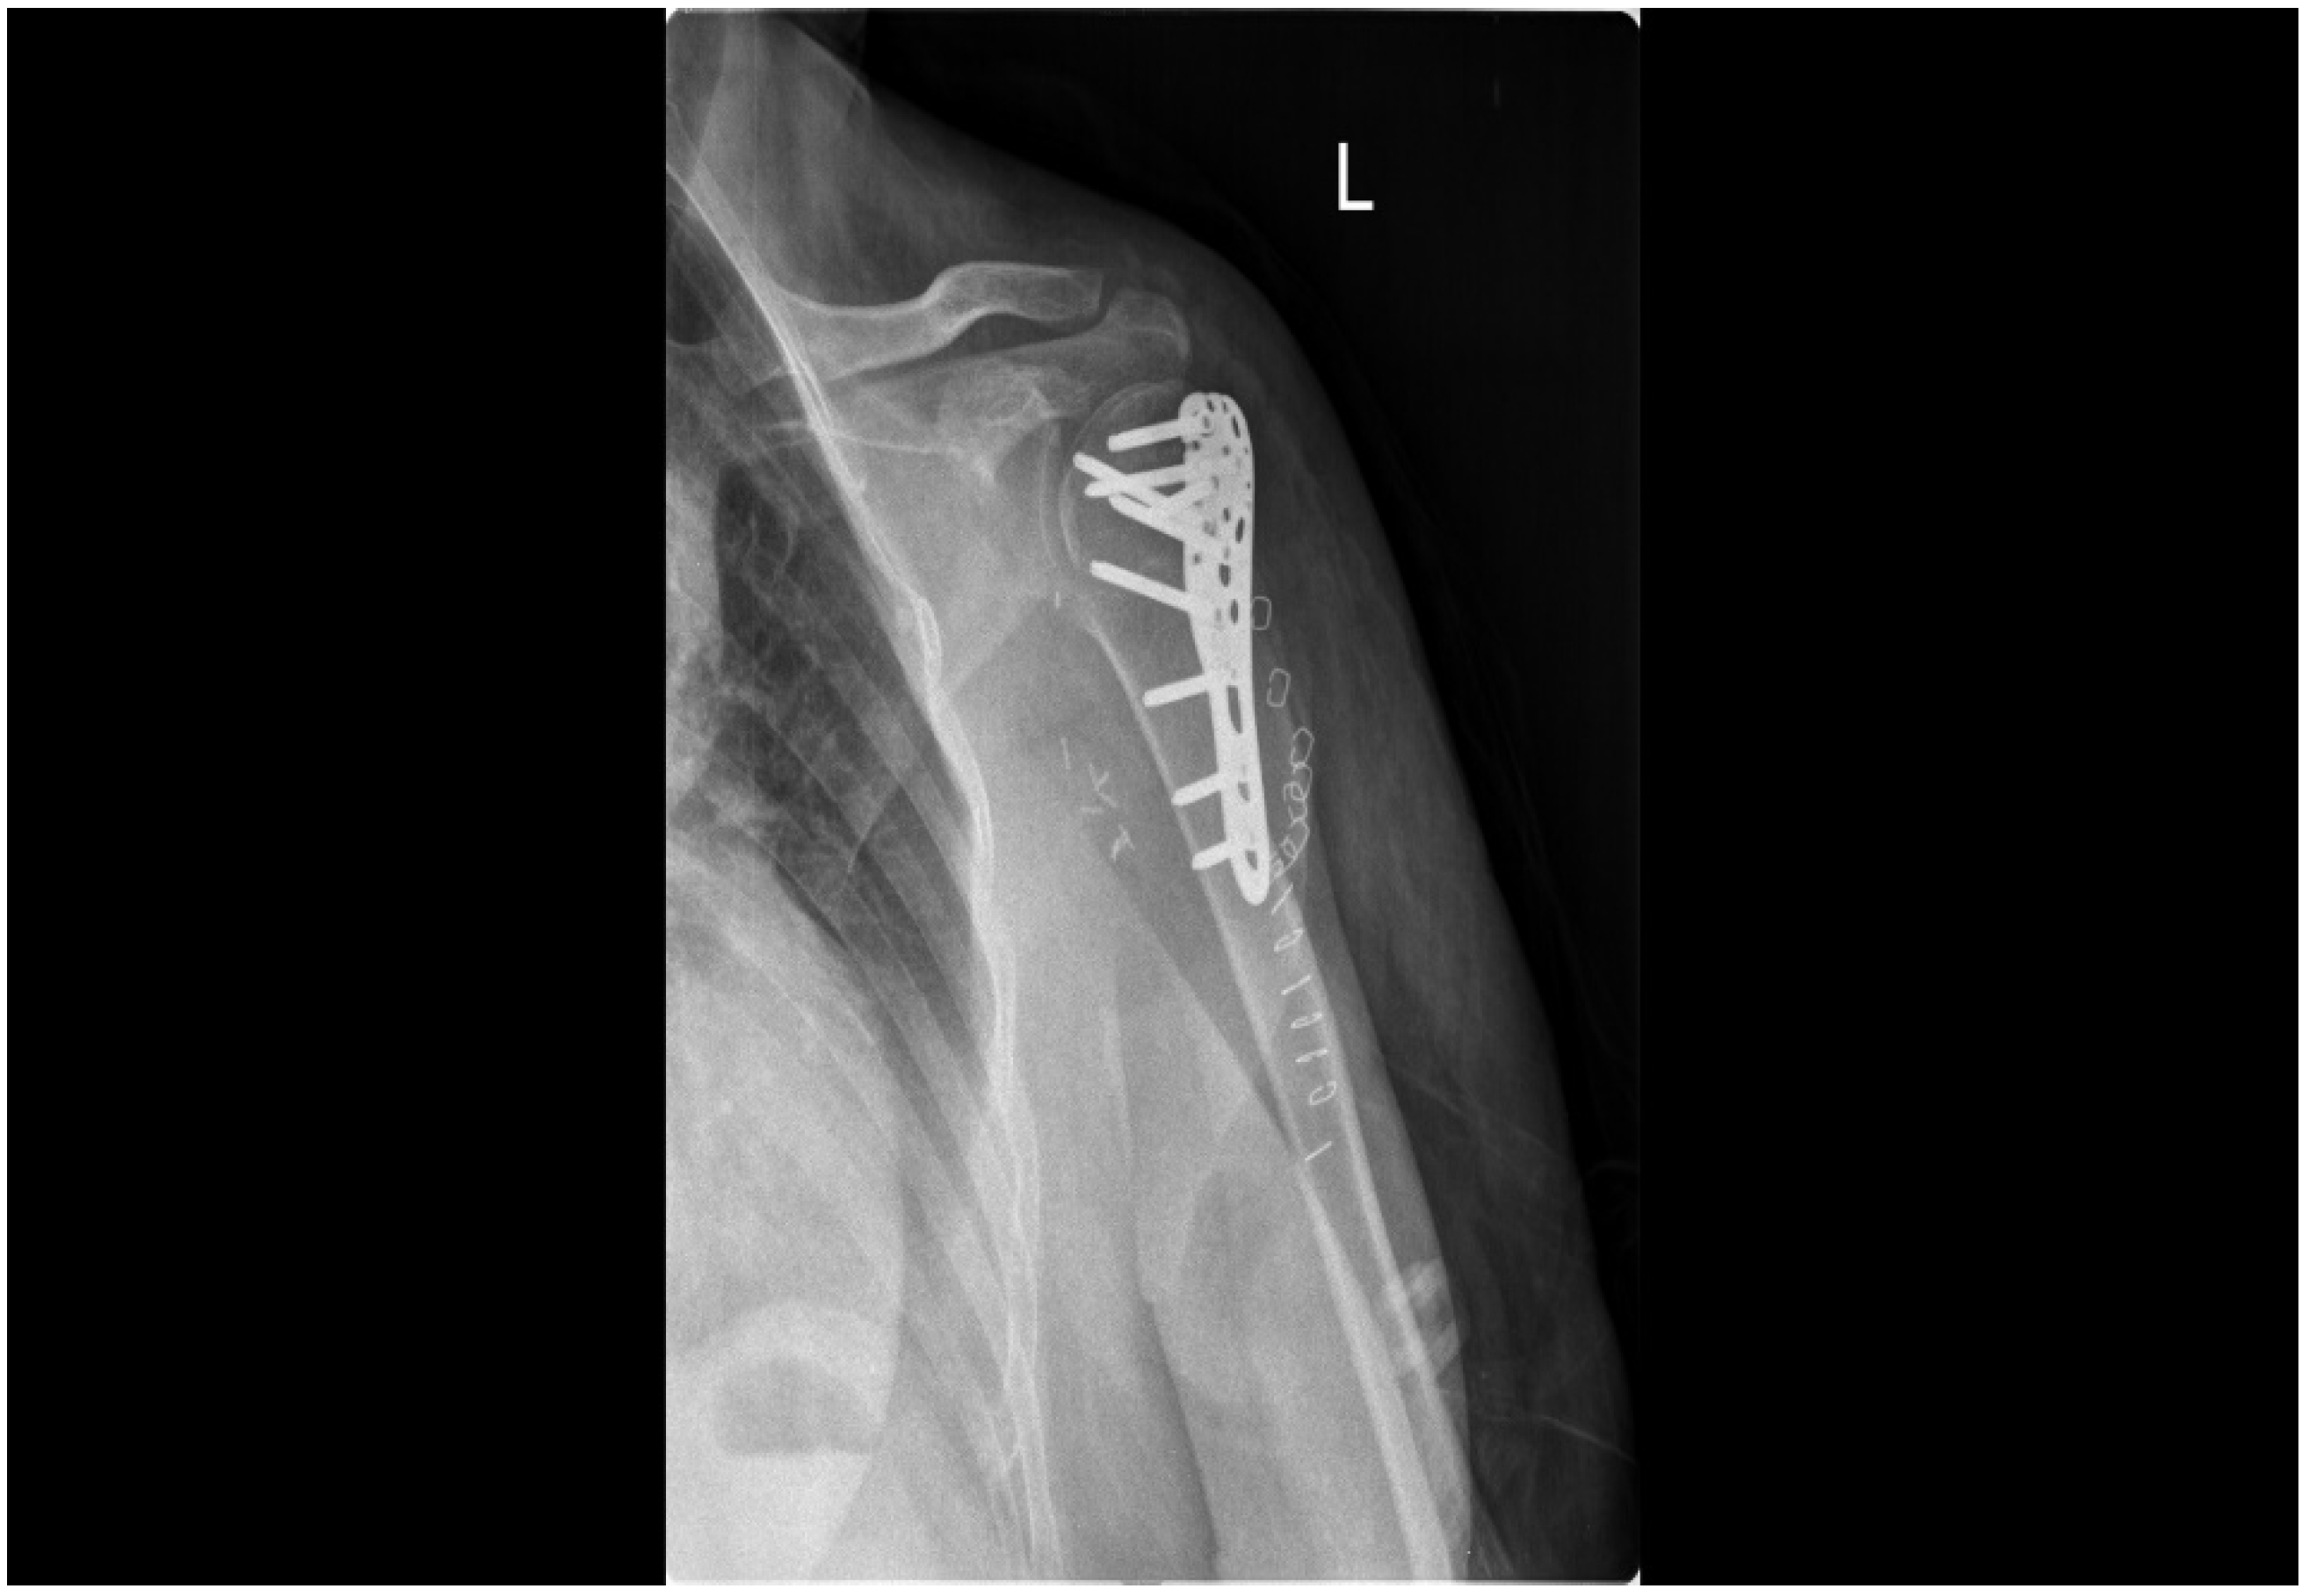

2.4. Treatment Modalities

2.2. Imaging Studies

2.5. Follow-Up